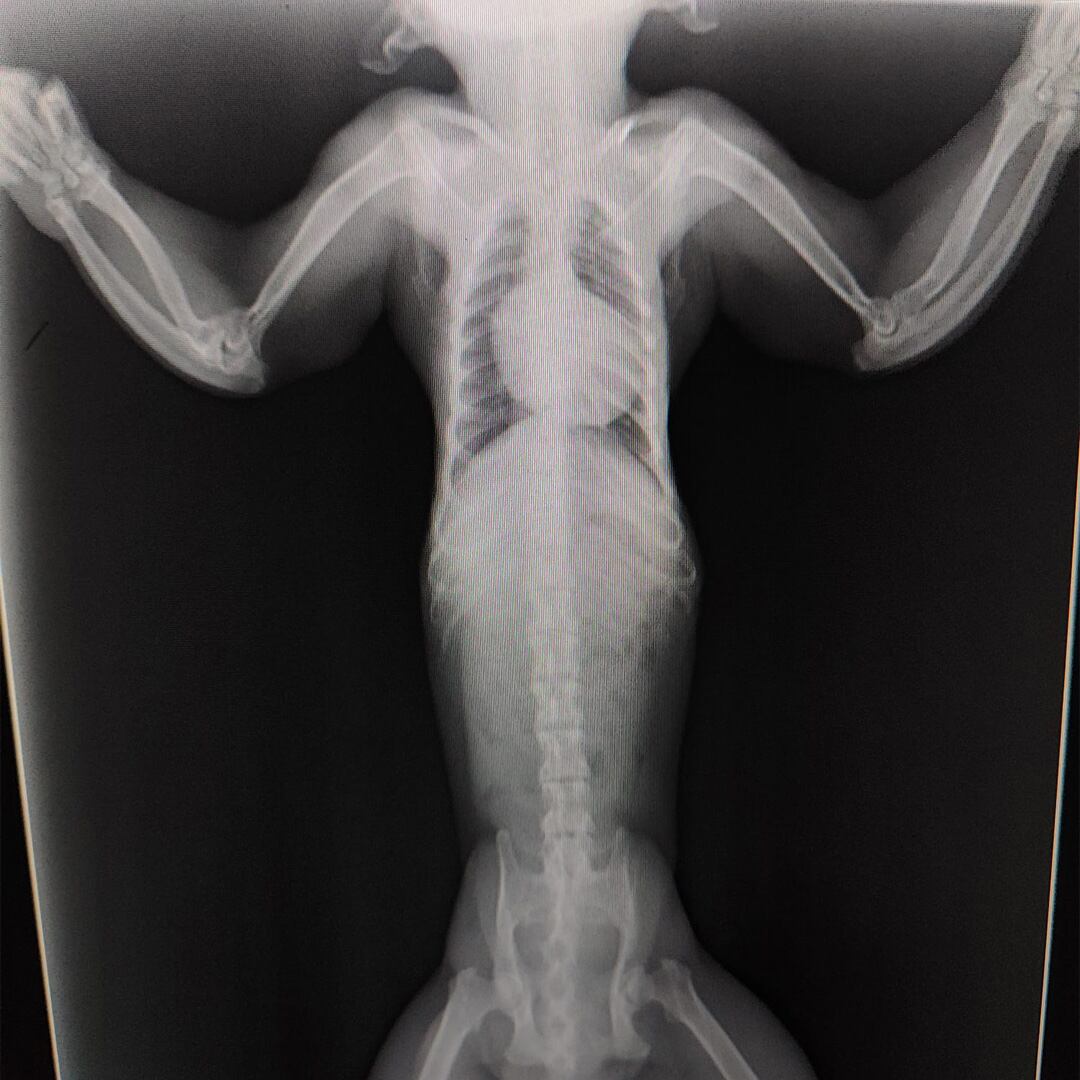

Pero lo que más ha preocupado es la revisión tras los rayos X. El pobre animal, presenta una enfermedad metabólica ósea, probablemente debida a una nutrición deficiente y falta de exposición solar que facilite la absorción de Vitamina D. Además, tiene señales de una posible fractura antigua en el antebrazo izquierdo.

Por otra parte, y durante la revisión veterinaria no se conseguía la extensión total de los brazos, por lo que, tras observar las radiografías, se confirmó artrosis y anquilosis en los codos.

Radiografía del animal / Primadomus4